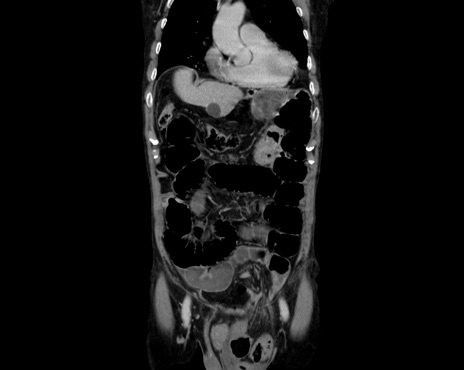

症例26(冠状断像)

【症例】80歳代男性

【主訴】嘔吐

【現病歴】昨晩2回嘔吐あり、今朝になっても嘔吐あり。来院。

【既往歴】胃潰瘍

【身体所見】意識清明、BT 37.6℃、BP 166/95mmHg、HR 100bpm、SpO2 97%、腹部:平坦・軟、腸蠕動音聴取良好、圧痛なし。

【データ】WBC 21900、CRP 1.4